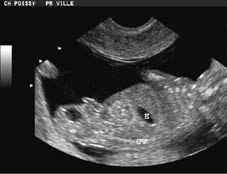

Corte sagital. Tumor heterogéneo tipo I, de ecogenicidad mixta. Estómago (E), columna vertebral (CV) e intestino (I). El sacro debe ser desproyectado para estudiar su probable compromiso.